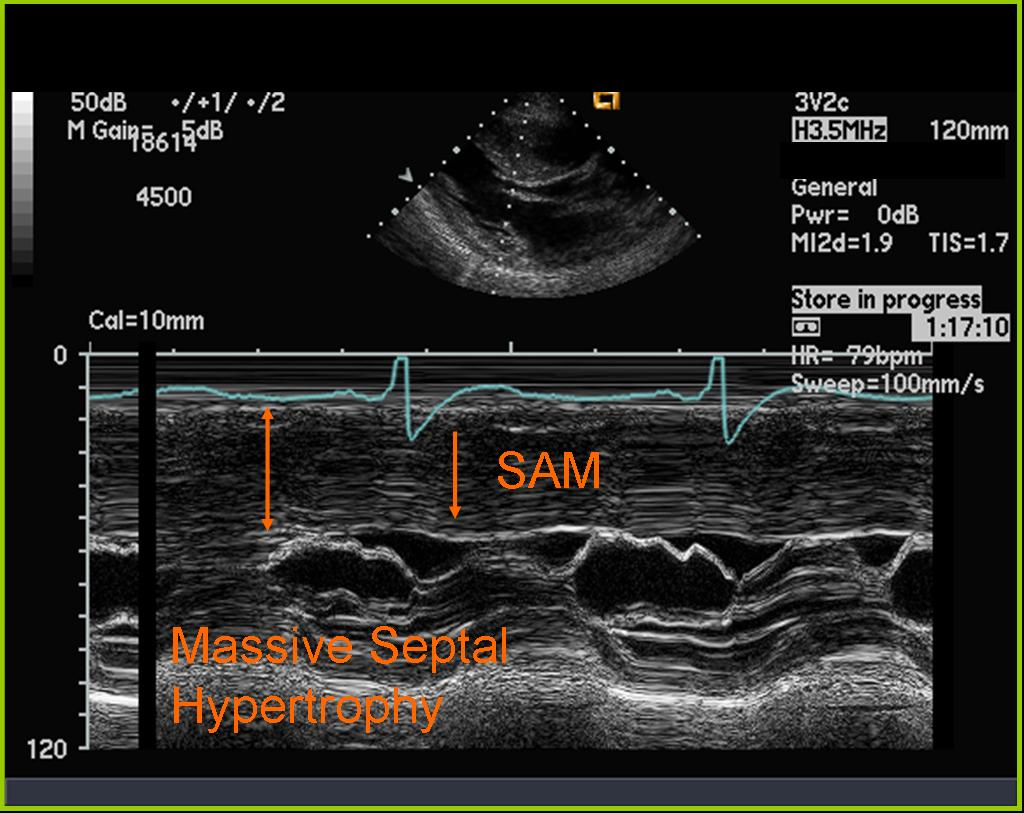

Systolic anterior motion of MV

HOCM

What is seen in this 2D image?

What condition is it seen in?